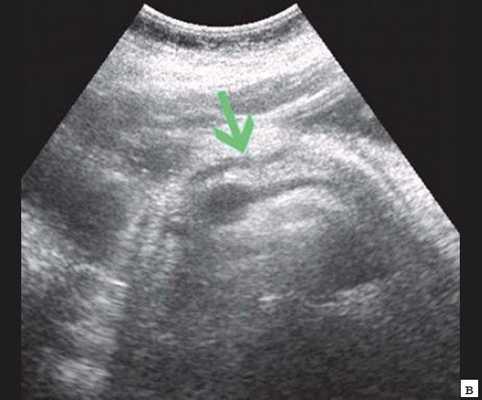

Если низкий блок обусловлен индуративным панкреатитом, при УЗИ имеет место увеличение органа в размере, могут выявляться кальцинаты в ПЖ (рис. 3). При опухоли головки ПЖ на фоне билиарной гипертензии визуализируется объемное образование в ПЖ (рис. 4). Критериями гипертензии главного панкреатического протока служит его расширение более 2 мм в теле и более 3 мм в головке ПЖ.

Рис. 4. Ультразвуковая картина опухоли головки ПЖ: образование в головке ПЖ (красная стрелка), расширенный панкреатический проток (зеленая стрелка).

в) Расширение панкреатического протока (зеленая стрелка).